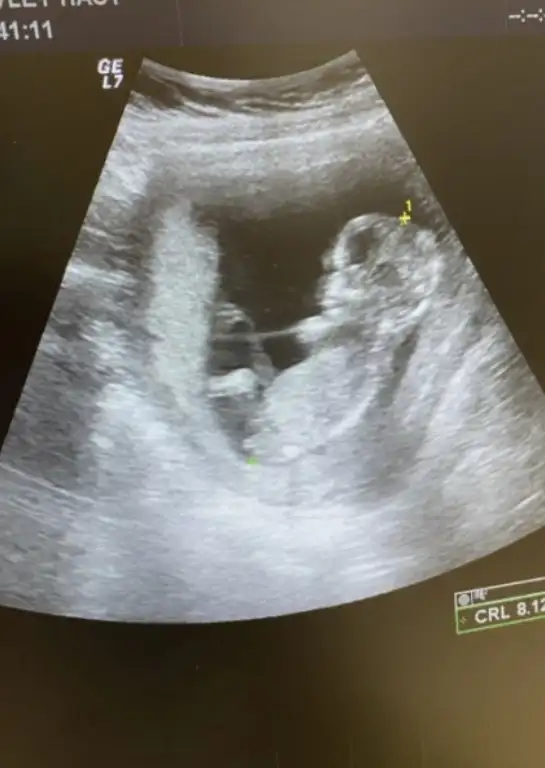

Kız gibi canımMerhabalar, sizce cinsiyeti ne olabilir? yorum yapabilir misiniz lütfen?8+3 karından ultrason.

Benımkine sizce?Kız gibi canım![]()

Karından usg miBenımkine sizce?

Evet karındanKarından usg mi

Kıza benzettim canımEvet karından

Canım kız bebek gibi ama tam emin olamadımMerhaba rica etsem bizede bir tahmin yapar mısınız?![]()